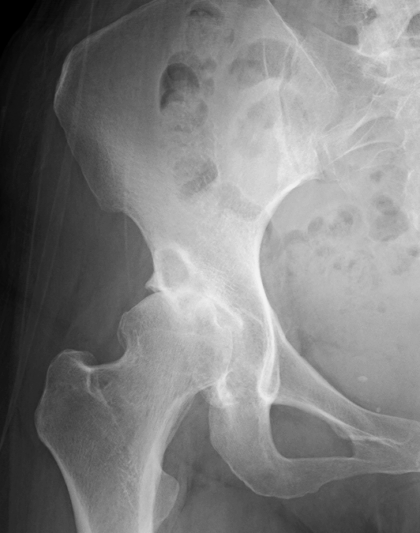

画像検査

X線(レントゲン)検査が基本となり、関節軟骨の厚みの減少(関節の隙間の狭小化)、骨棘(こつきょく:骨のトゲ)、骨嚢胞(こつのうほう:骨の中にできる空洞)の形成などを確認します 。必要に応じて、MRI検査で軟骨や周囲の軟部組織の状態をより詳細に評価します 。血液検査は、他の炎症性疾患との鑑別のために行われることがあります。

病期分類

X線所見に基づき、病気の進行度を前期、初期、進行期、末期のように分類し、それぞれの段階に応じた治療方針を決定します。